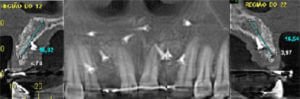

iniciou-se a avaliação do leito cirúrgico a ser implantado. As imagens da Tomografia evidenciaram uma atrofia importante da espessura,

comum aos pacientes de agenesia, que não possuem o desenvolvimento natural do rebordo alveolar pela ausência do dente permanente. Um procedimento cirúrgico foi realizado para regenerar o rebordo alveolar por vestibular e por palatino, com técnica de regeneração óssea guiada ,utilizando-se osso autógeno coletado do mento, associado a matriz inorgânica de osso bovino, e recoberto com membrana colágena fixada com micro parafusos.

Após 9 meses, imagens tomográficas evidenciam o volume alcançado com o procedimento reconstrutivo,